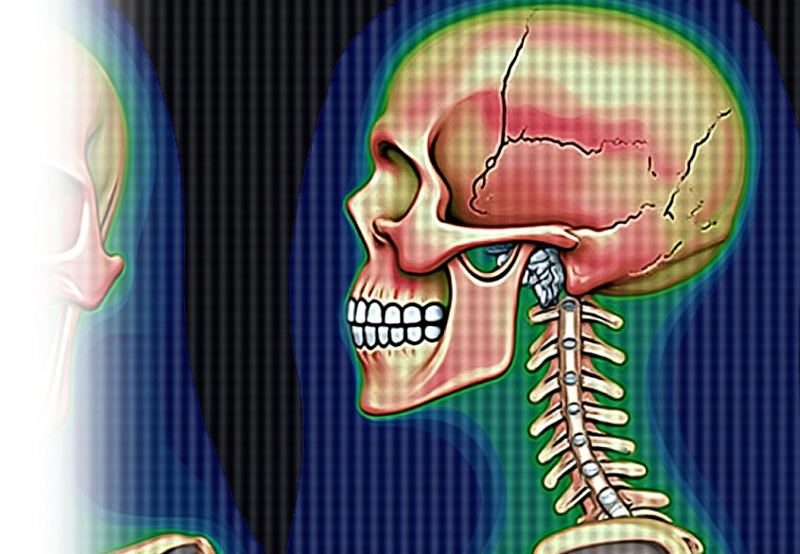

Показания для проведения КТ височных костей:

- воспалительные, опухолевые, травматические изменения височных костей;

- оценка тонких анатомических деталей строения, в т.ч различных аномалий внутреннего и среднего уха, наружного слухового прохода;

- метод выбора при кондуктивной тугоухости (при нейросенсорной тугоухости целесообразно проведение МРТ);

- при подозрении на холестеатому;

- при острых и хронических заболеваниях среднего уха.

Как проводится КТ височных костей?

Перед исследованием пациент снимает с себя все металлические украшения, в том числе очки и съемные зубные протезы. Исследуемый ложится на стол сканера, который постепенно перемещается в аппарат. Во время сканирования следует лежать неподвижно, чтобы получаемые трехмерные изображения были четкими и неискаженными.